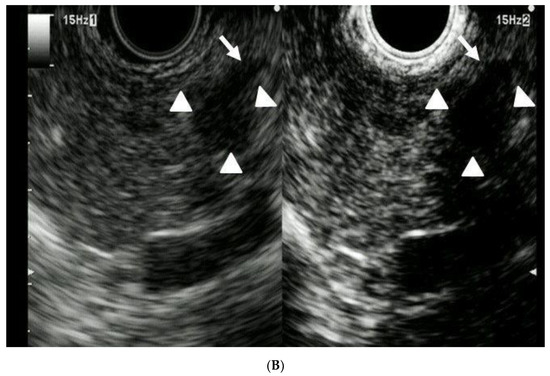

- Sakamoto, H.; Kitano, M.; Suetomi, Y.; Maekawa, K.; Takeyama, Y.; Kudo, M. Utility of contrast-enhanced endoscopic ultrasonography for diagnosis of small pancreatic carcinomas. Ultrasound Med. Biol. 2008, 34, 525–532. [Google Scholar] [CrossRef]